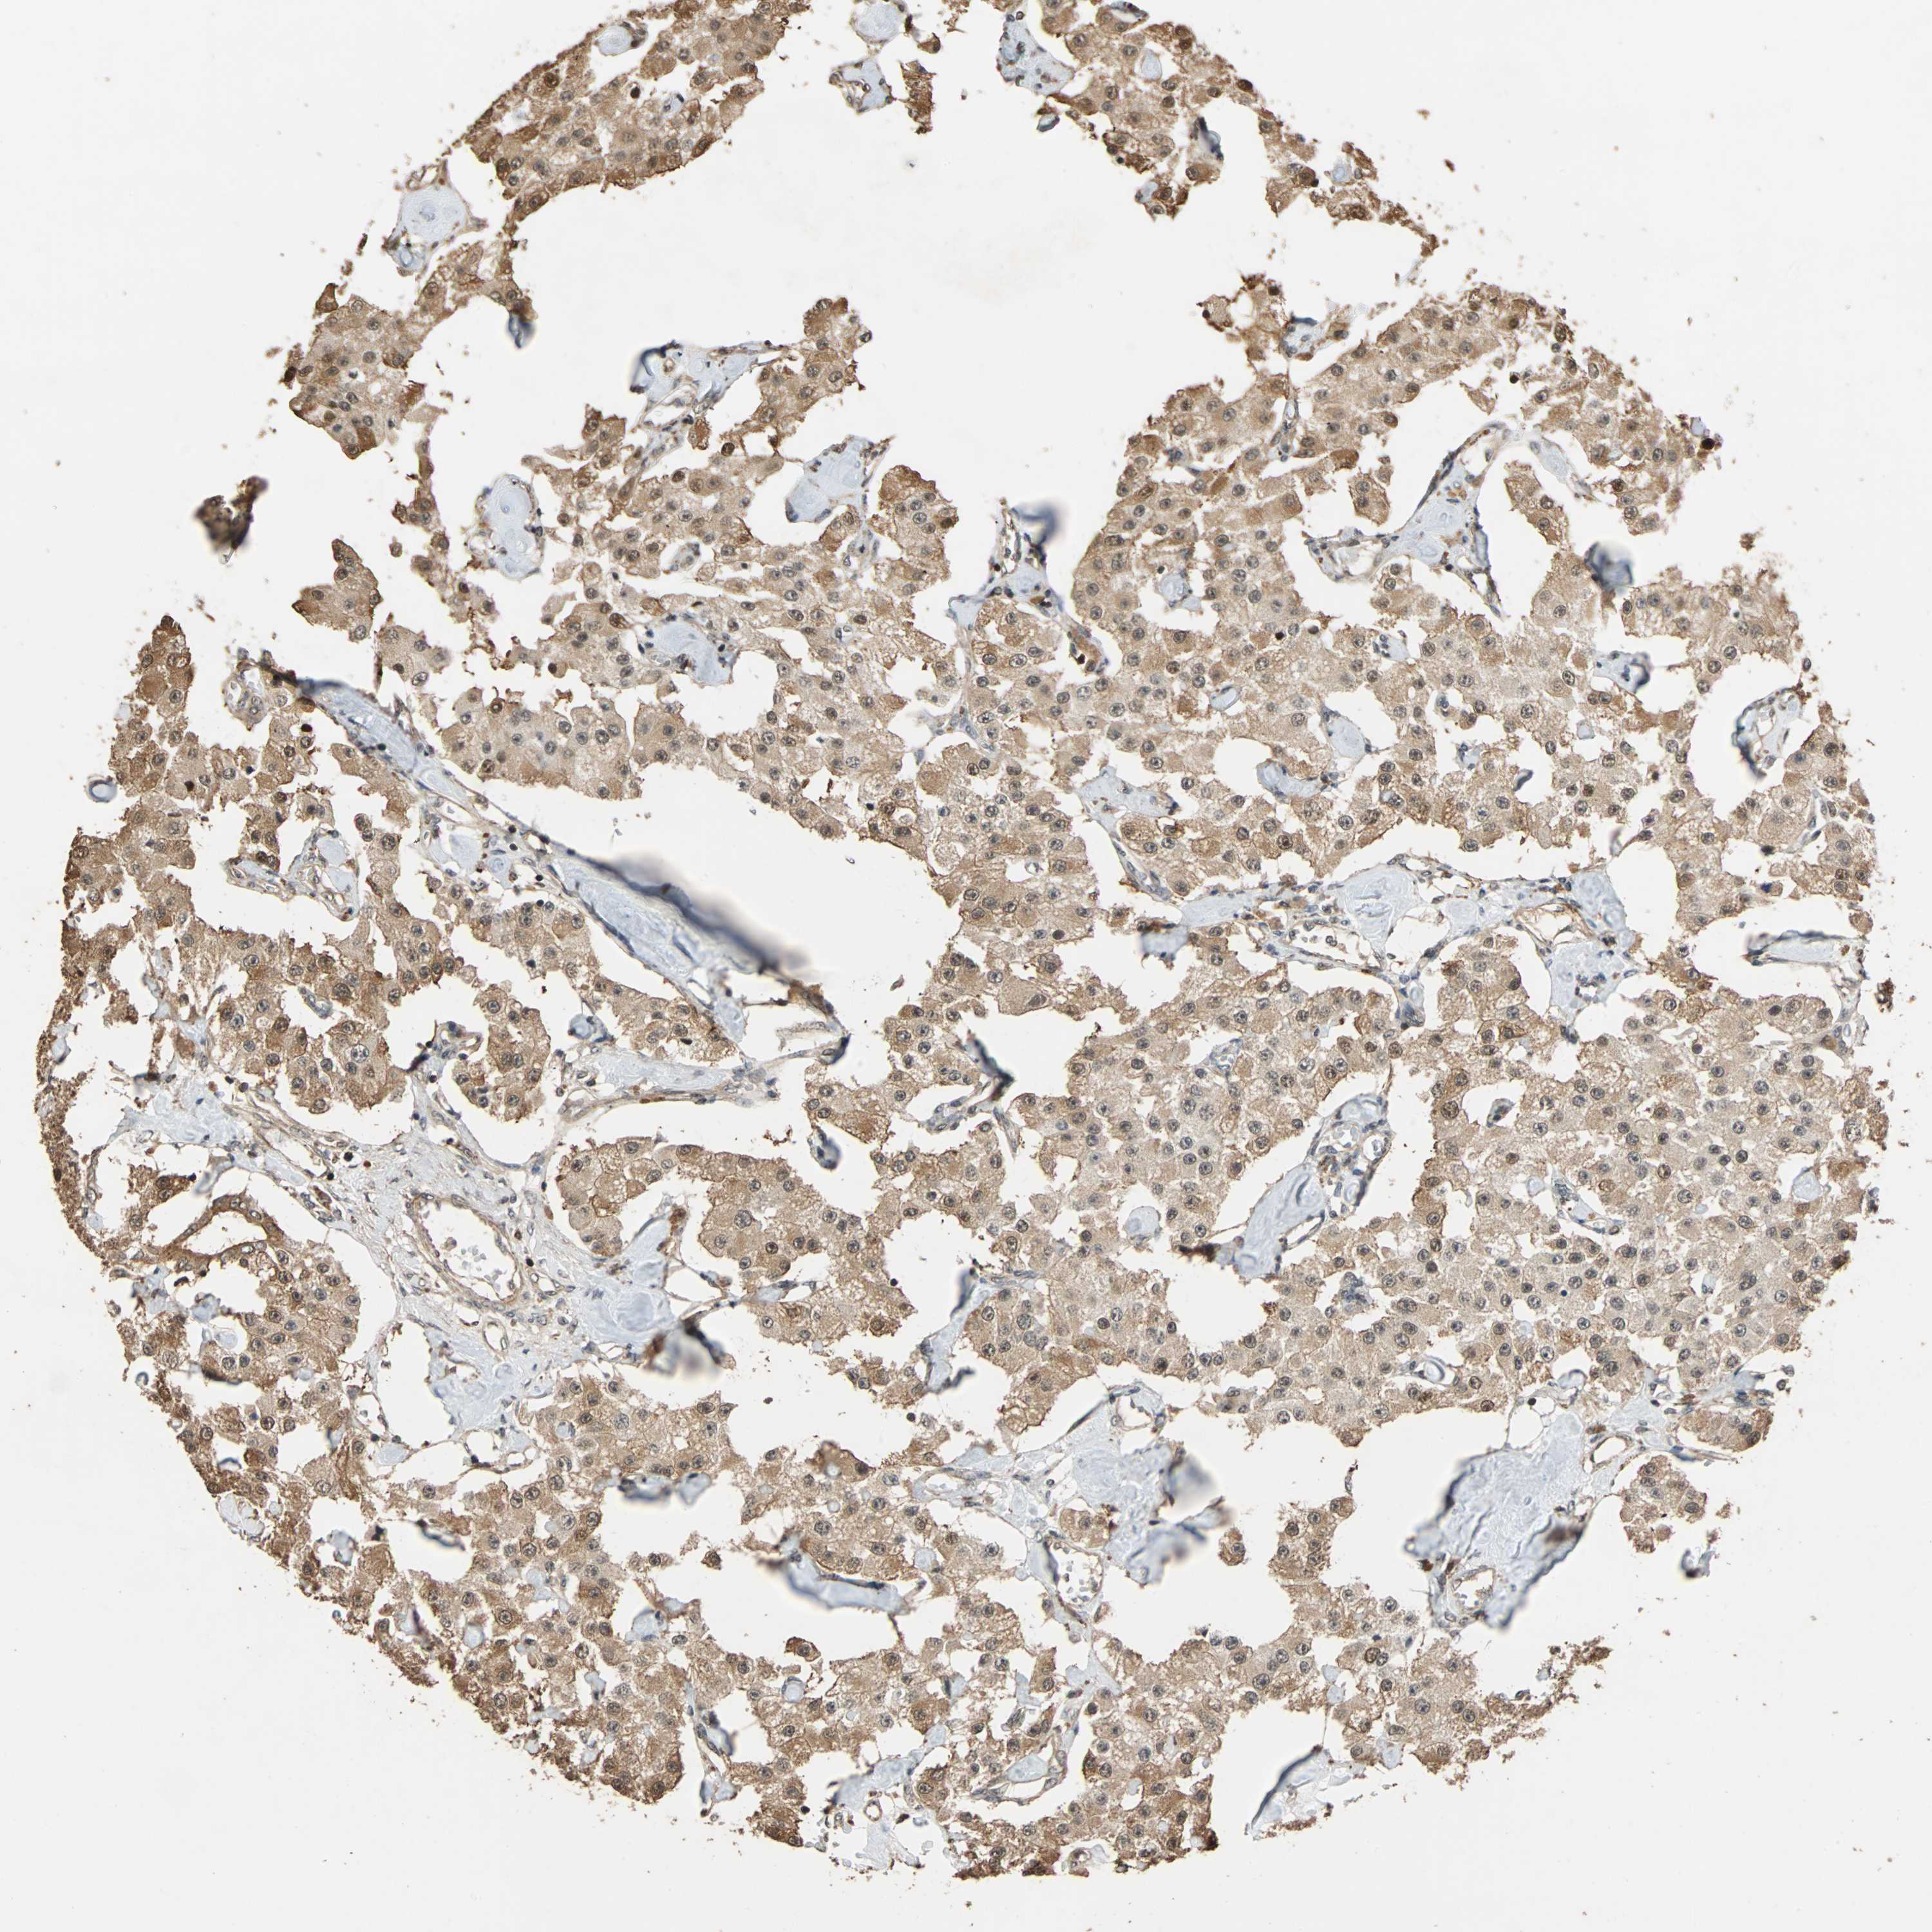

CARCINOID - Protein expressioni

A mouse-over function shows sample information and annotation data. Click on an image to view it in a full screen mode. Samples can be filtered based on level of antibody staining by selecting one or several of the following categories: high, medium, low and not detected. The assay and annotation is described here.

Each image is clickable and will lead to virtual microscopy that enables deeper exploration of all samples and also displays staining intensity scores, fraction scores and subcellular localization as well as patient and tissue information for each sample.

Antibody HPA006302

Staining

High

Medium

Low

Not detected

Intensity

Strong

Moderate

Weak

Negative

Quantity

>75%

75%-25%

<25%

None

Location

Nuclear

Cytoplasmic/membranous

Cytoplasmic/membranous,nuclear

Carcinoid, malignant, NOS